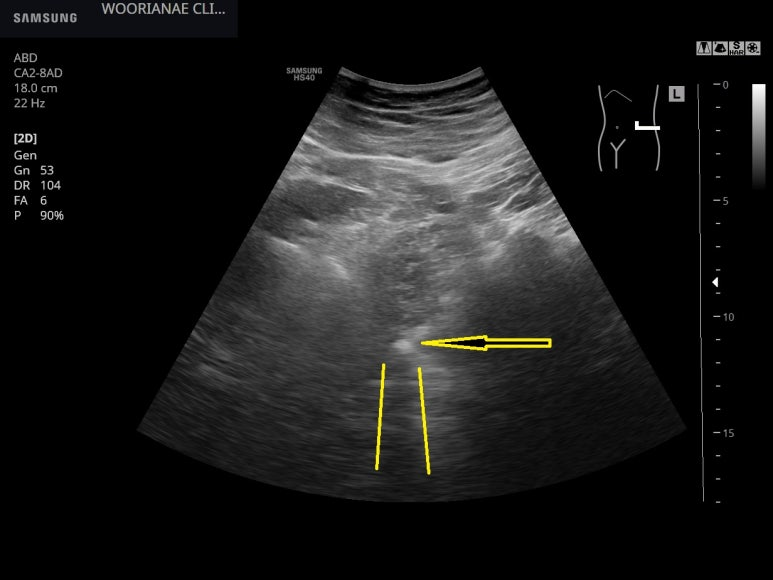

초음파 시행

좌측 신우에 뚜렷한 수신증 소견

확장된 요관을 따라가다 보면 요로결석이 관찰이 된다. 이렇게 보기까지 프로브를 적절하게 움직이는 노력이 필요하다.

postaccoustic shadowing이 뚜렷하니 석회화된 결석